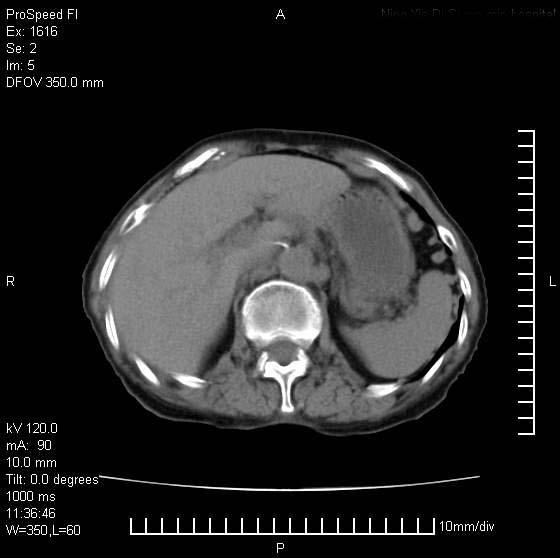

患者无明显临床症状,肝左叶发现一个圆形密度不均的低密度灶,边界较清楚,大小37x45mm,ct值35-70,患者犹豫做增强,如有增强片,我再发上,现先请各位老师会诊.

左肝外叶可见较大圆形低密度影,病灶可见较光整清晰边界,病灶内可见多量条状稍高密度影,右肝前叶亦可见圆形结节状低密度影,边界清晰,密度均匀,考虑1肝多发囊肿,左肝囊肿内出血2肝包虫病3左巨块型肝癌出血合并右肝转移或合并右肝囊肿

左肝外叶可见较大圆形低密度影,病灶可见较光整清晰边界,病灶内可见多量条状稍高密度影

考虑:肝包虫病

肝左叶类圆形低密度影,内可见略高密度影,边界清晰周边可见环形低密度带,考虑肝腺瘤可能,建议增强扫描除外肝血管瘤与肝癌

肝左叶不均匀占位,内有斑片状高密度出血灶,内侧缘似有假包膜,腹主动脉周围及肝门区结构紊乱,似有增大淋巴结,考虑:肝左叶hcc并淋巴结转移。建议增强扫描除外其他。